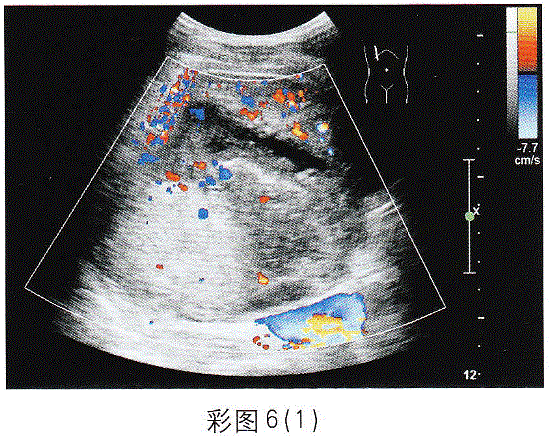

问题 临床资料:男,73岁,自述右上腹压痛伴寒战、高热;无肝炎、肝硬化病史,半年前查体B超显示肝脏未见异常。 超声综合描述: 图1、彩图6(1):肝右叶可见12.2cm×8.3cm不均质回声区,边界尚清,内回声明显不均,由无一低一增强回声,CDFI:周边可见点条状血流信号。 图2、彩图6(2):2周后复查:肝右叶可见10.3cm×8.3cm不均质回声区,内无回声范围较前明显增大,且形态不规则,CDFI:不均质回声区内未见血流信号,周边可见条状血管绕行。 {图2} {图3} 超声提示: